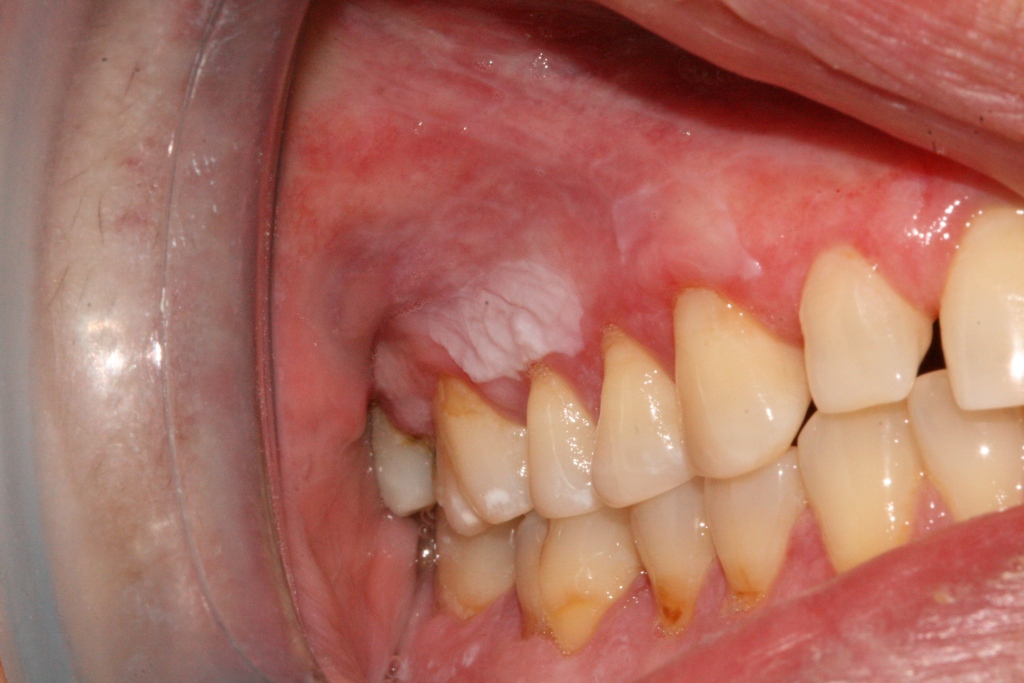

La leucoplasia oral (del griego leykós, blanco y plasía, proliferación) es una lesión bucal que presenta histológicamente algunas disqueratosis, como: papilomatosis; hiperqueratosis; y acantosis, cuya característica principal es ser una placa blanquecina que normalmente no puede desprenderse por raspado, forma parte del epitelio, y está en crecimiento.

Es blanca porque presenta un engrosamiento epitelial con hiperproducción de queratina. Es una lesión delimitada y asociada a factores que la provocan, sobre todo el tabaco; dejando el consumo de este hábito, puede llegar a remitir. También la lesión puede aparecer en zonas no queratinizadas -suelo bucal, lengua- por lo cual se recomienda hacer siempre biopsia; es complejo saber a simple vista si una lesión es cáncer o leucoplasia.